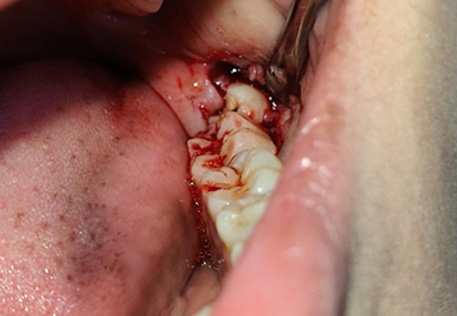

Surgical Extraction: For impacted or partially erupted wisdom teeth, performed with precision by our skilled oral surgeons.

Painless Procedure: Local anesthesia or sedation options for a comfortable experience.

Fast Recovery: Minimal downtime with post-treatment care guidance for a smooth healing process.

Before / After